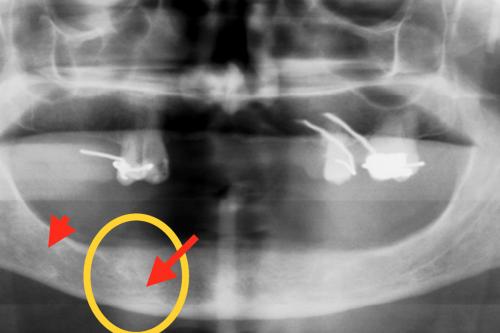

La eficacia clínica de la técnica de elevación atraumática sinusal con Cortical-Fix ®

Las conclusiones del presente estudio preliminar de investigación indican que el Cortical-Fix ® constituye un avance importante para el implantológo al proporcionar un método predecible para la inserción de los implantes dentales.